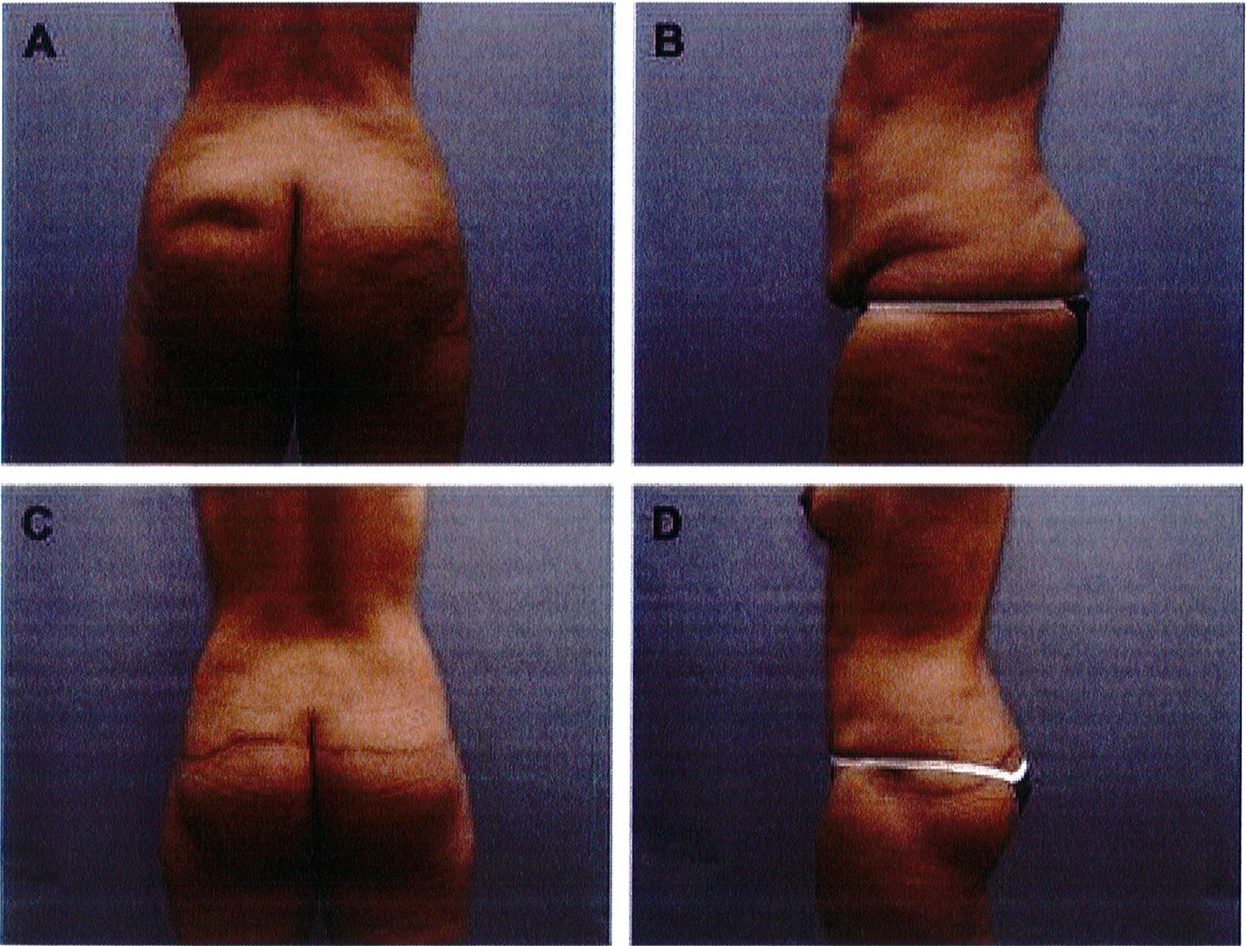

đại. Những vết sẹo này có thể được điều trị bằng các thủ thuật sửa sẹo thông thường hoặc phẫu thuật cắt bỏ. Chúng tôi chưa từng gặp trường hợp nào bị nhiễm khuẩn hoặc hoại tử mỡ sau phẫu thuật. Bệnh nhân sau phẫu thuật đa số hài lòng với kết quả của mình. Sự gia tăng thể tích mông và dựng được điểm hình chiếu là những ưu điểm độc đáo mà phương pháp này mang lại so với kỹ thuật tạo hinh vùng mông kinh điển (Hình 11-13).

Chúng tôi đã thực hiện kỹ thuật này cho hơn 40 bệnh nhân, tính tới thời điểm hiện tại. Có thể nói, với bất kỳ quy trình tạo hình cơ thể nào, tình trạng nhão/ chùng da cũng sẽ xuất hiện sau một thời gian nhất định. Tuy nhiên, trong kỹ thuật này, điểm hình chiếu và gò mông được tạo ra vẫn đươc duy trì theo thời gian. Biển chứng thường gặp nhất là tách vết mổ và sẹo phì

Hình. 11. (A, B) Bệnh nhân nữ 59 tuổi với vùng da mông chùng và xệ. (C,D) Hai năm sau phẫu thuật tạo hình thành bụng và tạo hình mông bằng phương pháp purse-string.Bênh nhân này bị tách vết mổ, sau đó đã đươc điều tri liền seo

Hình. 12. (A, B) Bệnh nhân nữ 37 tuổi với vùng mông dẹt và xệ. (C,D) Tám tháng sau phẫu thuật tạo hình thành bụng và tạo hình mông bằng phương pháp purse- string .

Hình. 13. (A, B) Một bệnh nhân 62 tuổi với vùng mông xệ và hình chiếu không thẩm mỹ. (C,D) Sau phẫu thuật 16 tháng tạo hình mông bằng phương pháp purse-string (đã tao hình thành bung trước đó).